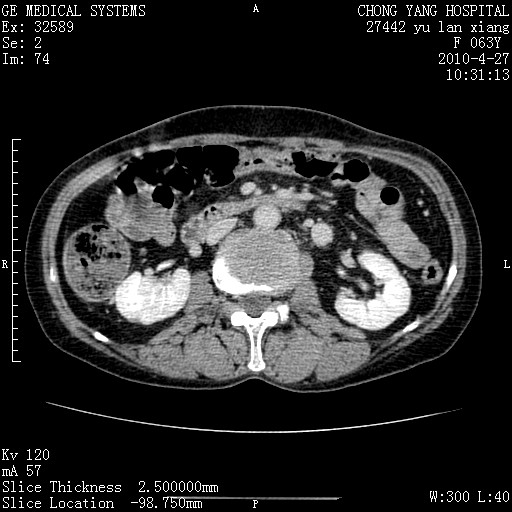

标题: CT26066:F63Y 上腹正中压痛半月,CA199:7400u/ml,MR示胰腺炎伴 [打印本页]

胰腺癌侵犯腹腔动脉干-分支、胃壁、左侧膈肌伴胰周及腹膜后淋巴结转移、胆囊切除术后。

胰腺癌侵犯腹腔动脉干-分支、胃壁、左侧膈肌伴胰周及腹膜后淋巴结转移、胆囊未显影。